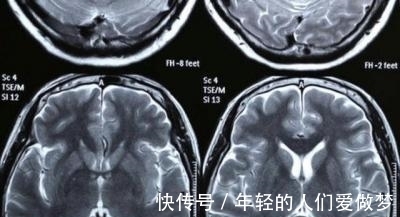

女孩的父母觉得亲戚的话虽然不太好听,但是说得也有道理,于是女孩的父母就带女孩去医院检查,到医院后医生就给女孩的脑部进行拍片,果然女孩的脑袋的确和别人不一样,接下来医生的话让父母吓出了一身冷汗,医生对女孩的父母说:”女孩之所以记忆力那么好,是因为女孩患有记忆力强迫症,这种病症是会产生焦虑,长此以往对脑部会产生影响,而且脑部是天生长成这样的,要治疗很困难”这几句话仿佛晴天霹雳,没想到这样聪明绝顶的女儿居然是因为患这种病。